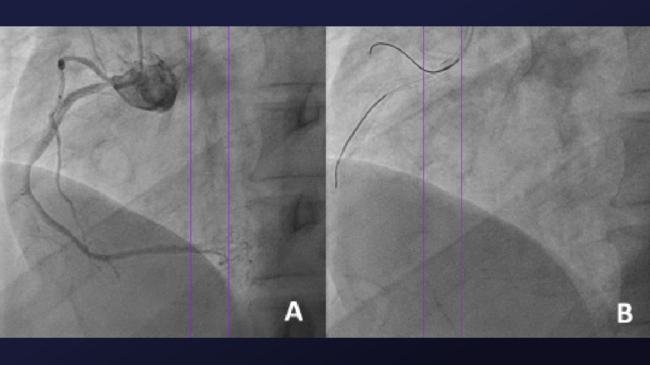

A 56-year-old man with exertional angina underwent coronary angiography, which showed severe restenosis within a previously placed stent in the ostial right coronary artery (RCA). Selective engagement of the RCA with a JR4 diagnostic catheter was difficult due to excessive protrusion of the previous stent into the aorta (Figure 1A). A 6-Fr, JR4 guide catheter was used for intervention.

A workhorse guidewire was able to enter the conus branch through a protruding side-strut. Wiring the RCA proved difficult and could only be done through a protruding side-strut (Figure 1B). A Sasuke dual-lumen catheter (DLC; Asahi Intecc) was loaded onto the RCA guidewire, but the central stent lumen could not be wired successfully (Figure 1C). The DLC was then loaded onto a floating wire, and the central stent lumen was successfully accessed with a second guidewire (Figure 1D; Video Series).